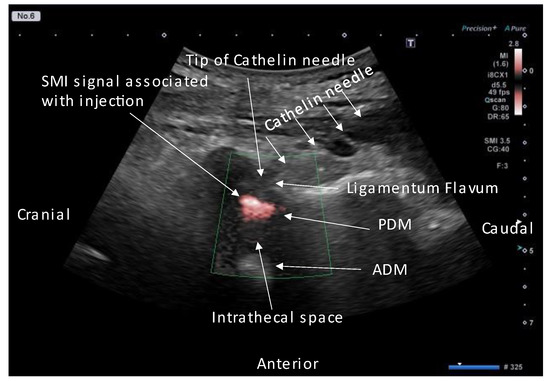

2. Technique Description

- Accurate needle tip guidance into the ligamentum flavum behind the epidural fat layer;

- Palpation of resistance by finger sense during ligamentum flavum insertion while confirming with sonography;

- Confirmation of the position of the needle tip in the ligamentum flavum;

- Tracing the spread of the drug in the epidural space using SMI during the injection.